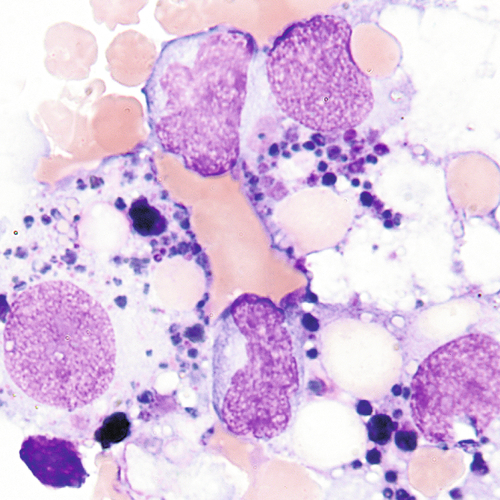

Macrophage with engulfed RBCs. RBCs are digested by enzymatic activity within the macrophage. The digestive process causes the RBCs to lose color and to appear as vacuoles within the cytoplasm of some macrophages.

Large cells with eccentric nuclei and vacuolated cytoplasm may be present in all body fluids. They may be seen with or without inclusions, such as RBCs, siderotic granules, or lipids.